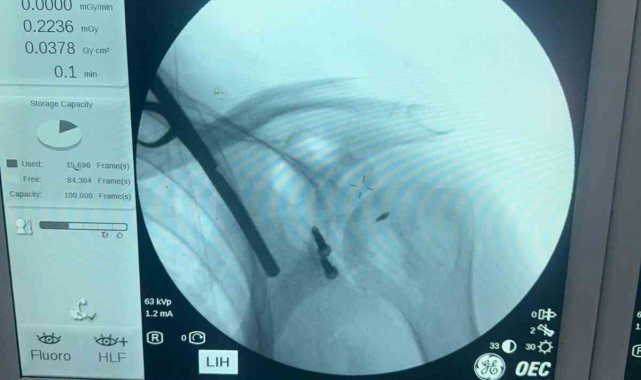

Balıkesir Atatürk Şehir Hastanesinde ilk defa Latarjet Omuz ameliyatı gerçekleştirildi. Balıkesir İl Sağlık Müdürlüğü'nden yapılan basın açıklamasında daha önceden yaklaşık on beş defa omuzu çıkan ve başka İllerde bulunan özel hastanelerde üç defa ameliyat olan hasta şikayetlerinin geçmemesi ve omuzunun tekrar çıkması üzerine Balıkesir Atatürk Şehir Hastanesi Ortopedi ve Travmatoloji Kliniğine başvurdu. Hastanın yapılan muayenesi ve tetkikleri sonucu, hastanın omuz ekleminde aşırı kemik dokusu kaybı mevcut olması sebebiyle "Latarjet omuz ameliyatı" planlandı. Balıkesir de ilk defa uygulanan bu yöntem Doç. Dr. Özgün Karakuş ve Op. Dr. Fatih Işık tarafından başarıyla gerçekleştirildi. Ameliyat sonrası sağlığına kavuşan hasta bir gün sonra taburcu edildi. İl Sağlık Müdürlüğü, "Ameliyat öncesi ve sonrası desteğini esirgemeyen anestezi ekibine, servis, ameliyathane ve yoğun bakım ekibine ve emeği geçen tüm çalışma arkadaşlarımıza teşekkür eder, hastamıza geçmiş olsun dileklerimizi iletiriz" açıklaması yaptı.

Latarjet prosedürü, travmatik omuz çıkığı (çıkıkları) sonrasında kemik hasarı oluşan bir omuza kemiksel stabilizasyon sağlamak için yapılan cerrahi bir prosedürdür. Ameliyat kemik kaybını geri kazandırır ve ön tarafta bir kas askısı sağlar. Latarjet ameliyatı, önemli kemik kaybı nedeniyle omuz instabilitesi (sabit olmayan) yaşayan hastalarda önemli ve sıklıkla önerilen bir omuz ameliyatıdır.